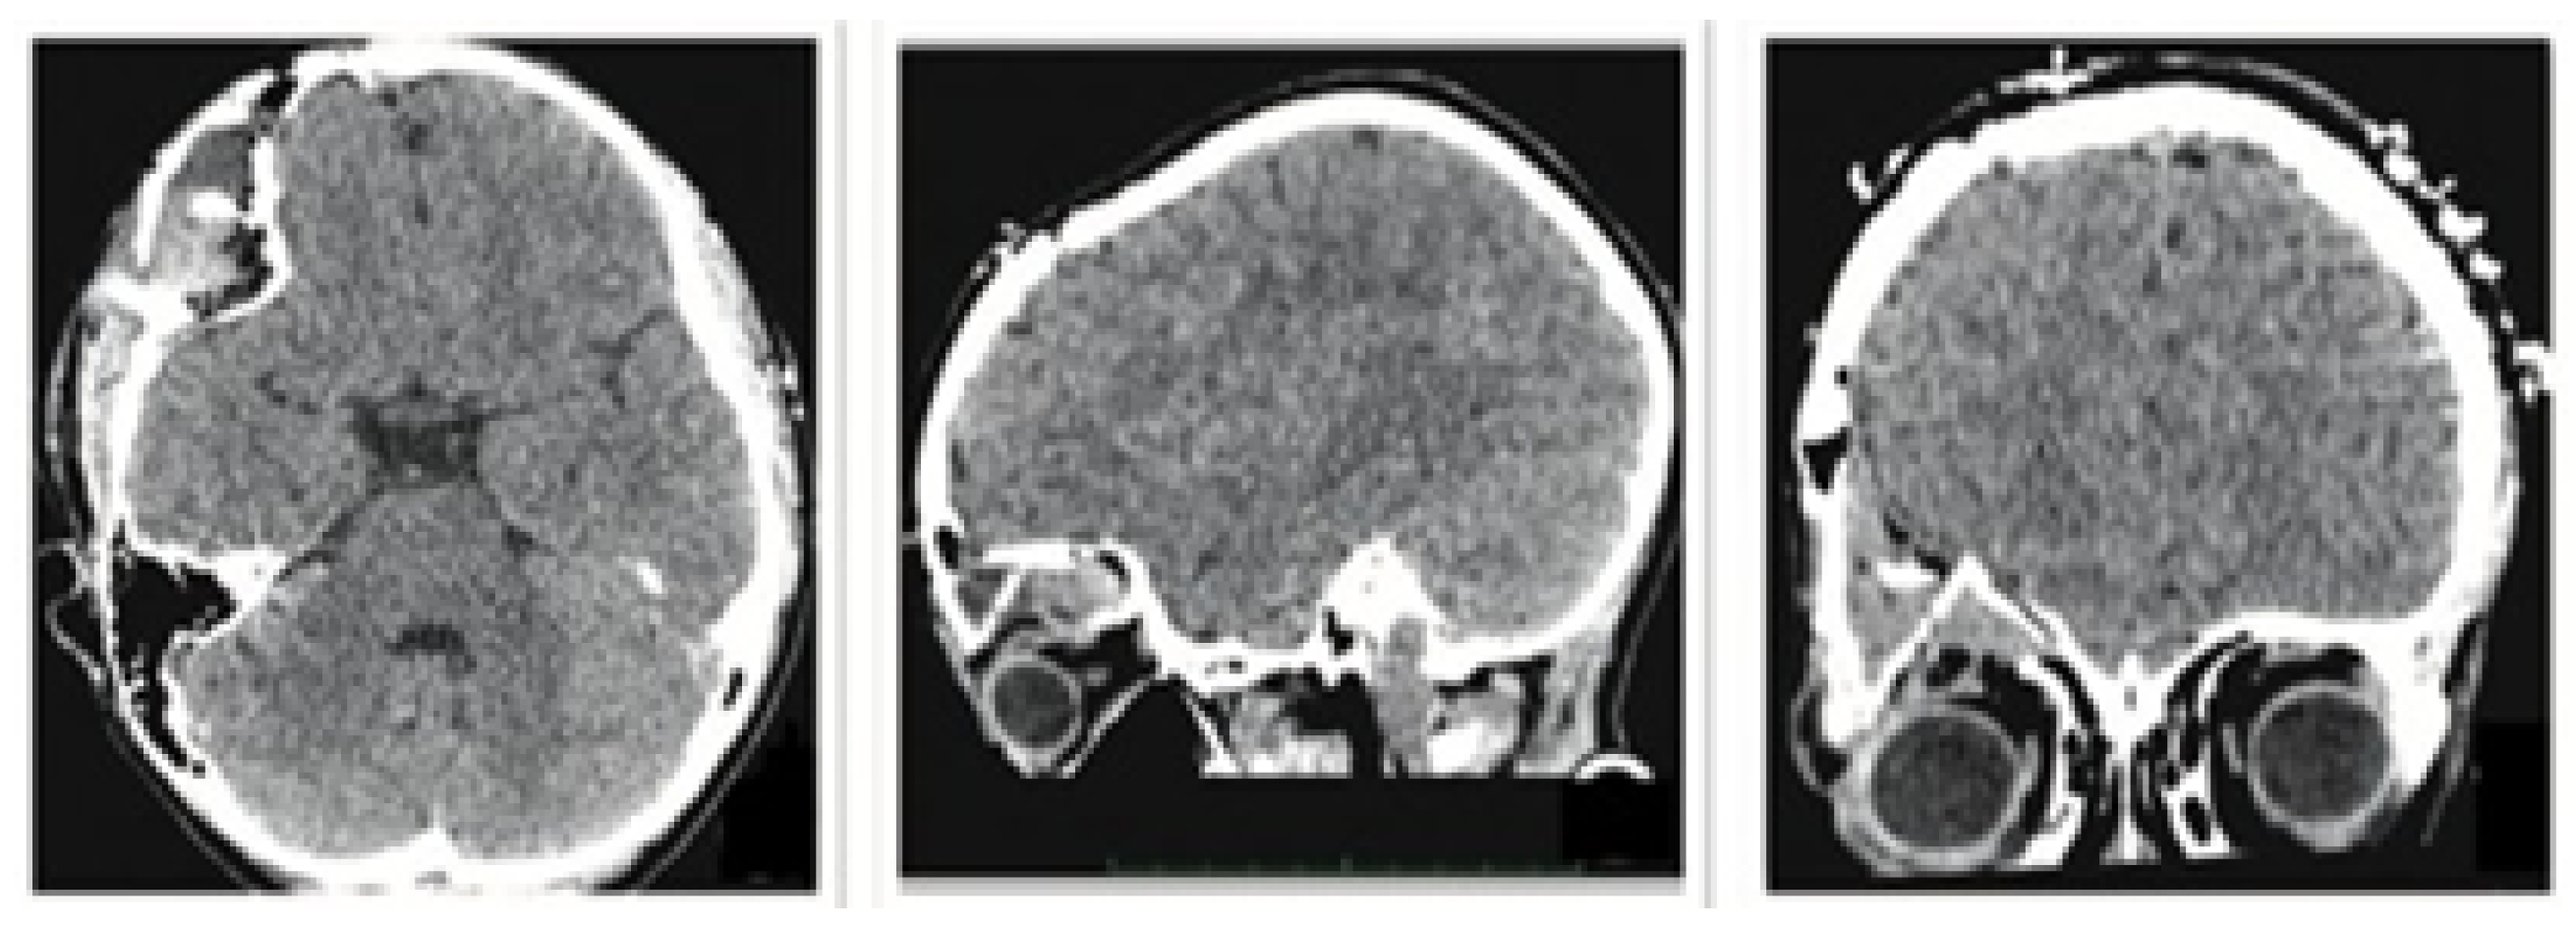

The patient was a 10-year-old male who sustained a cranial collapse in the left temporal-parietal-occipital region. This is a sequelae of cranioencephalic trauma, with multiple surgical interventions having been performed. A physical examination was conducted, which revealed subsidence in the temporo-parieto-occipital region, accompanied by some scars. Cerebral activity manifests itself externally, as evidenced by the visible transmission of light from the brain to the skin (see Figure 10). Upon tactile examination, the irregular edges of a bone defect resulting from an anterior craniotomy were palpable. A CT scan with 3D reconstruction was performed, where the solution of bone continuity in the affected area can be seen (Figure 11).

3.2.5. Postoperative Results

The postoperative results were positive and verified with the help of a new tomography, digital photography and physical examination. The complete reconstruction of the bone defect was achieved (see Figure 15 and Figure 16).

Figure 15. Postoperative tomographic control. The reconstruction process was successfully executed to a satisfactory degree.

Figure 16. Resolution of the cranial deformity.